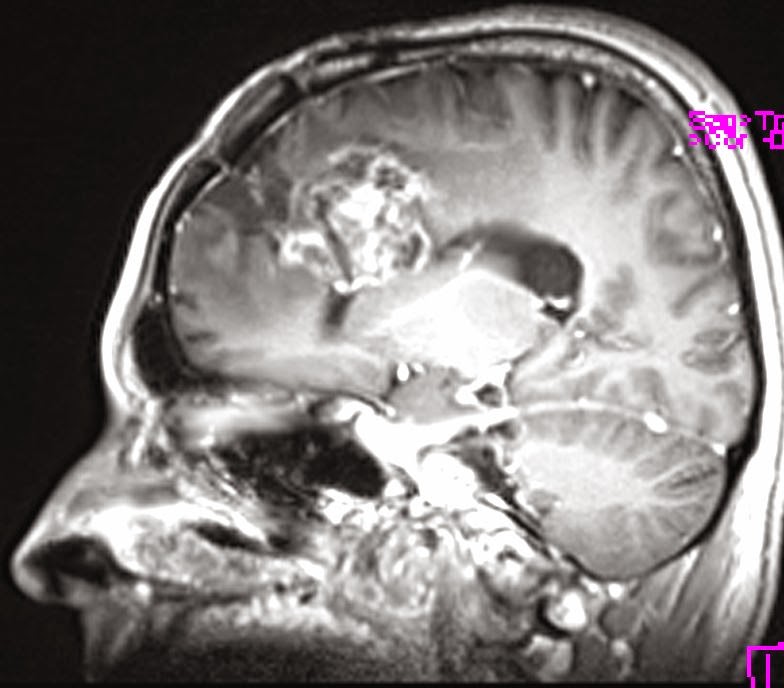

Összehasonlítva a 2014.02.10-i MR vizsgálattal:

A középvonalat balra kb. 1,5 cm-rel meghaladó és a corpus callosumot involváló jobb oldali frontalis inhomogén szerkeszetű és halmozású elváltozás mérete minden irányban mérsékelten csökkent, legnagyobb átmérője jelenleg kb. 5,6 x 5 x 4,7 cm. T2 súlyozásnál a laesio körül a hyperintenzitás kiterjedése főként dorsalis irányban enyhén csökkent. Az elülső frontalis műtéti behatolás mögött parasagittalisan a liquorhoz viszonyítva magasabb jelű bennéket tartalmazó cystosus elváltozás mérete hasonló a korábbihoz. Bal oldalon temporalis DVA* látható. A kamrarendszer frontális részeinek compressioja és dislocatioja lényegesen nem változott.

Vélemény: Enyhe méretcsökkenést mutató jobb túlsúlyú bifrontális tu. a corpus callosum infiltratiojaval.

*DVA: developmental venous anomaly (DVA) = cerebral venous angioma

Fejlődési eredetű (embrionális) vénás anomális = agyi vénás angióma (érdaganat)

Elkészült a kemoterápia alatti első MR-felvétel, és íme az eredménye:

Saját, műkedvelő fordításomban ez azt jelenti, hogy:

Jobb oldalon a corpus callosum, azaz kérgestest, amely nem más, mint a két agyféltekét összekötő rostköteg, és a gyrus cinguli, azaz az agyféltekék mediális, tehát középen elhelyezkedő felszínén található hosszú hajlított struktúra elülső részében elhelyezkedő térfoglalás nagysága érdemben nem változott, azonban a szélei jobban elhatárolódtak.

A mérsékelt fokú (hoppá! csak mérsékelt!!!) baloldali terjedés és a környező részben ödémás terület olyan, mint november 11-én volt. Az elülső és a frontális szarvak jobbra, lefelé nyomódtak össze. Továbbá az elülső szarvak hátsó fele olyan, mint volt: mérsékelten tágultak jobb túlsúllyal.

Ami jó hír: mérséklődött a középvonal balra íveltsége.

Mindazonáltal a jobb oldali árkok jobban ábrázolódnak.

A műtéti üreg a korábbihoz hasonló! Nem nőtt tovább a rohadék!!!

Az orvosi vélemény: Stabil állapot.